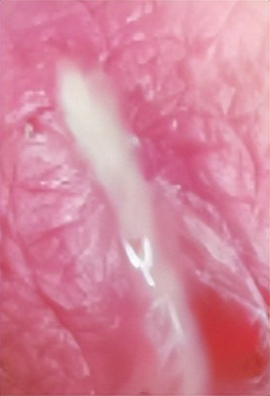

在生殖器和肛周部位长出“小菜花”

基本上长这样

小到1毫米大到数厘米都有可能

细小淡红色、湿润柔软

这一般就是感染HPV了